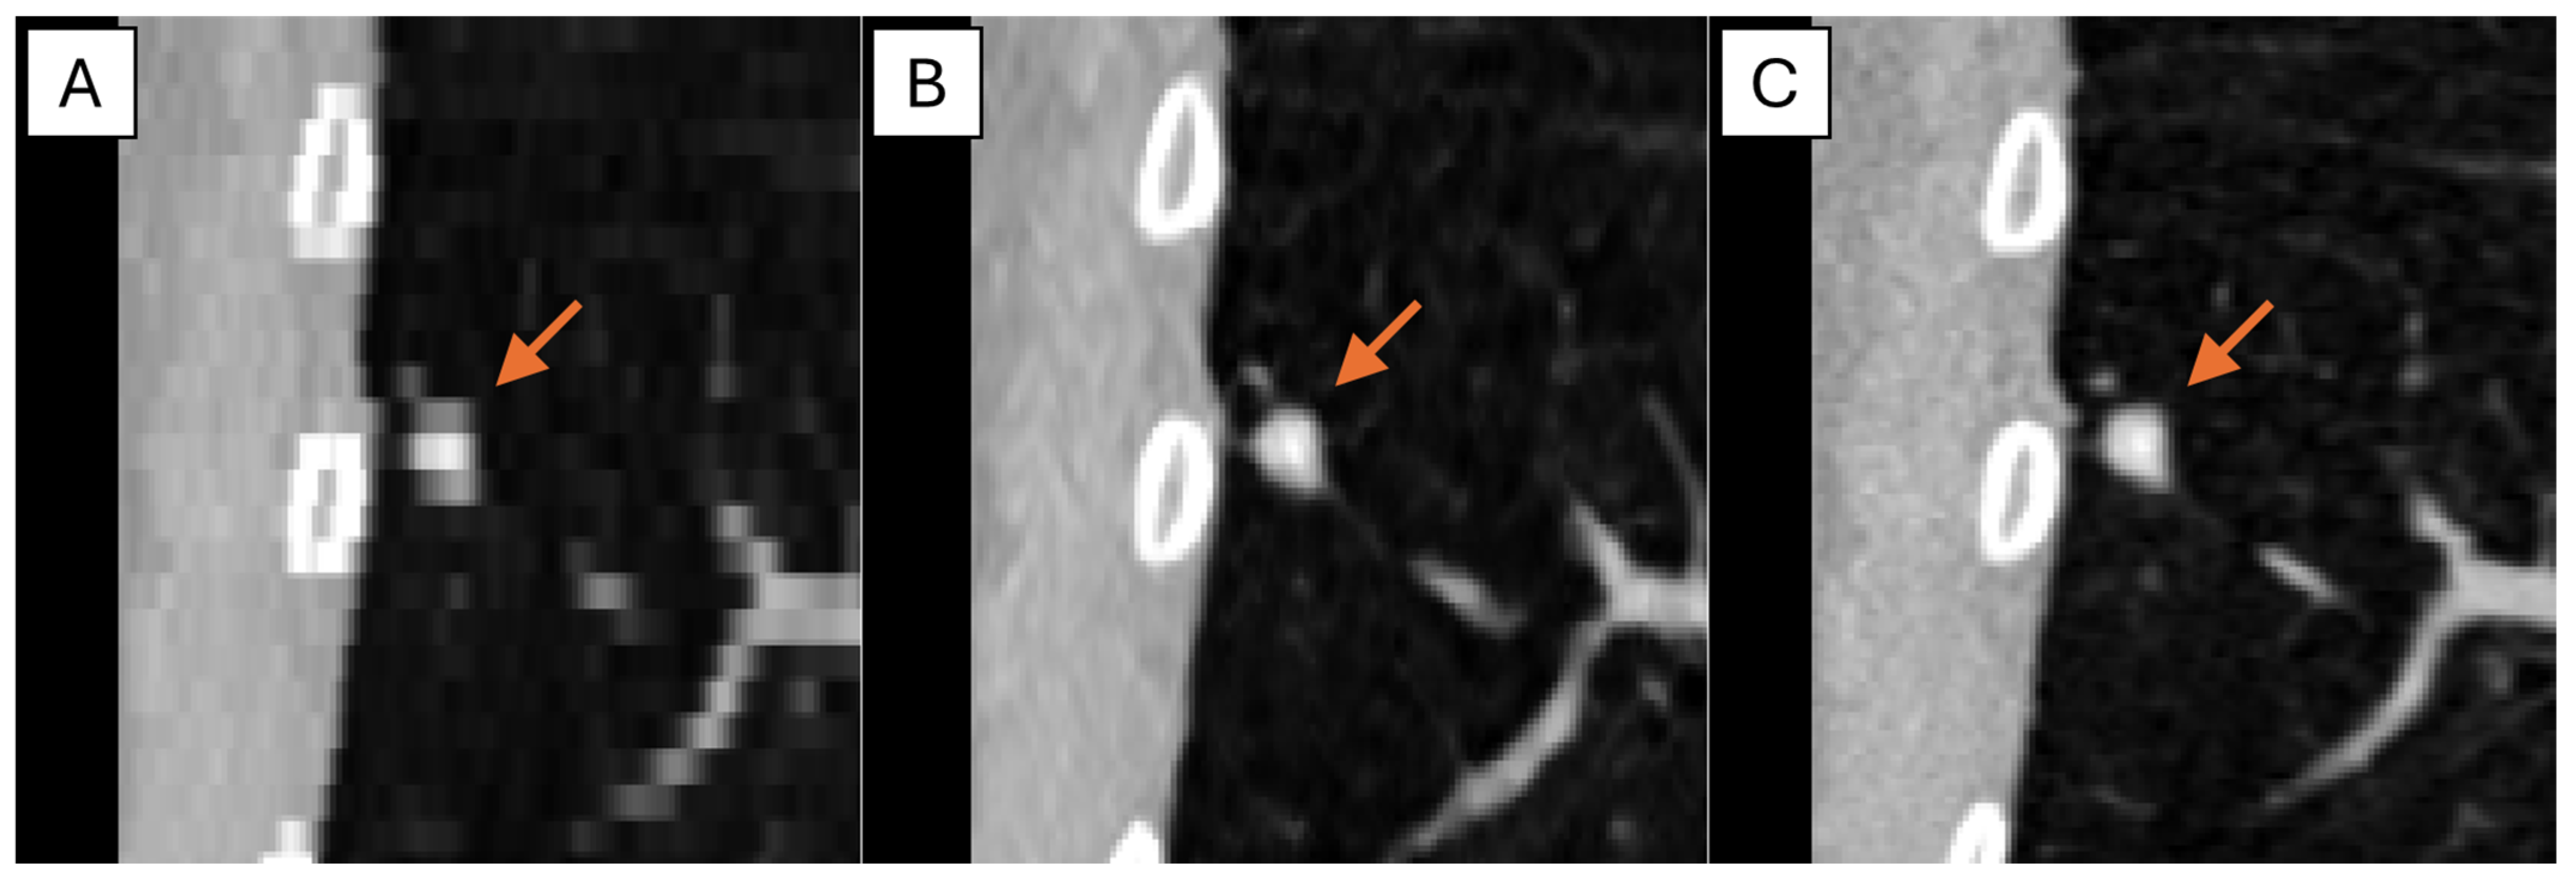

The representative thick-, generated-thin- and thin-slice coronal CT images of solid nodule and (ground glass nodule) GGN are shown in Figure 5 and Figure 6. The thick-slice CT images show staircase artifacts on both solid nodule and GGN, making accurate volume measurement and corresponding categorization nearly impossible, whereas generated-thin-slice CT images show image quality on par with thin-slice CT images, exhibiting clear nodule/GGN structures and well-defined pulmonary vessels delineations.

Figure 5. Coronal CT images of (A) thick-slice, (B) generated-thin-slice, and (C) thin-slice presenting solid nodules as shown by the arrows.